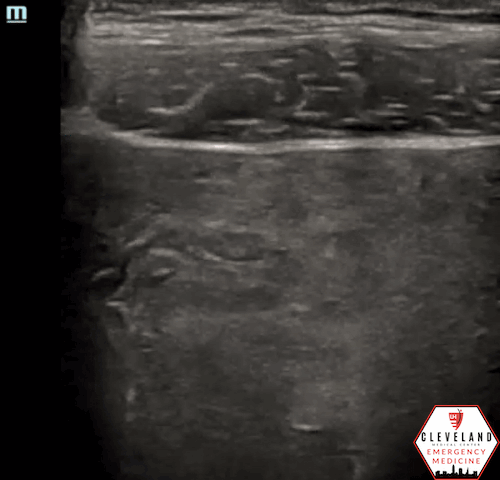

Linear probe

An intrauterine gestational sac was visualized with the transabdominal probe without obvious contents within it. However, with a high-frequency linear probe, a yolk sac and fetal pole was visualized, which confirmed an IUP. Flickering within the fetal pole suggested fetal heart beat. No free fluid was seen.

The Utility of a High-Frequency Linear Transducer

In pregnant patients with ~5-8 weeks gestational age, it may be difficult to clearly visualize an IUP with the commonly used low frequency probe. Based on a study by Tabbut et al, a high-frequency linear probe allowed for IUP confirmation in 33% of patients whose scans with a curvilinear probe were indeterminate. Additionally, of the 66% of pregnancies that could not be confirmed, 83% could also not be visualized by a transvaginal ultrasound exam and, thus, were most likely ectopic pregnancies [10]. While this was only a pilot study, these results suggest that a high-frequency linear probe may be useful in patients with first trimester vaginal bleeding and may significantly reduce the amount of transvaginal scans required in the ED. This reduction may ultimately help save the patient and the ED time, cost, and potential stress/complications from the procedure itself. A downside of the linear probe is that it is limited by body habitus due to depth restrictions.

Similar to the case above, these images illustrate the improved image quality with the linear probe (right) compared to the curvilinear probe (left)

Linear transducer able to detect pregnancy at 7 weeks [5]